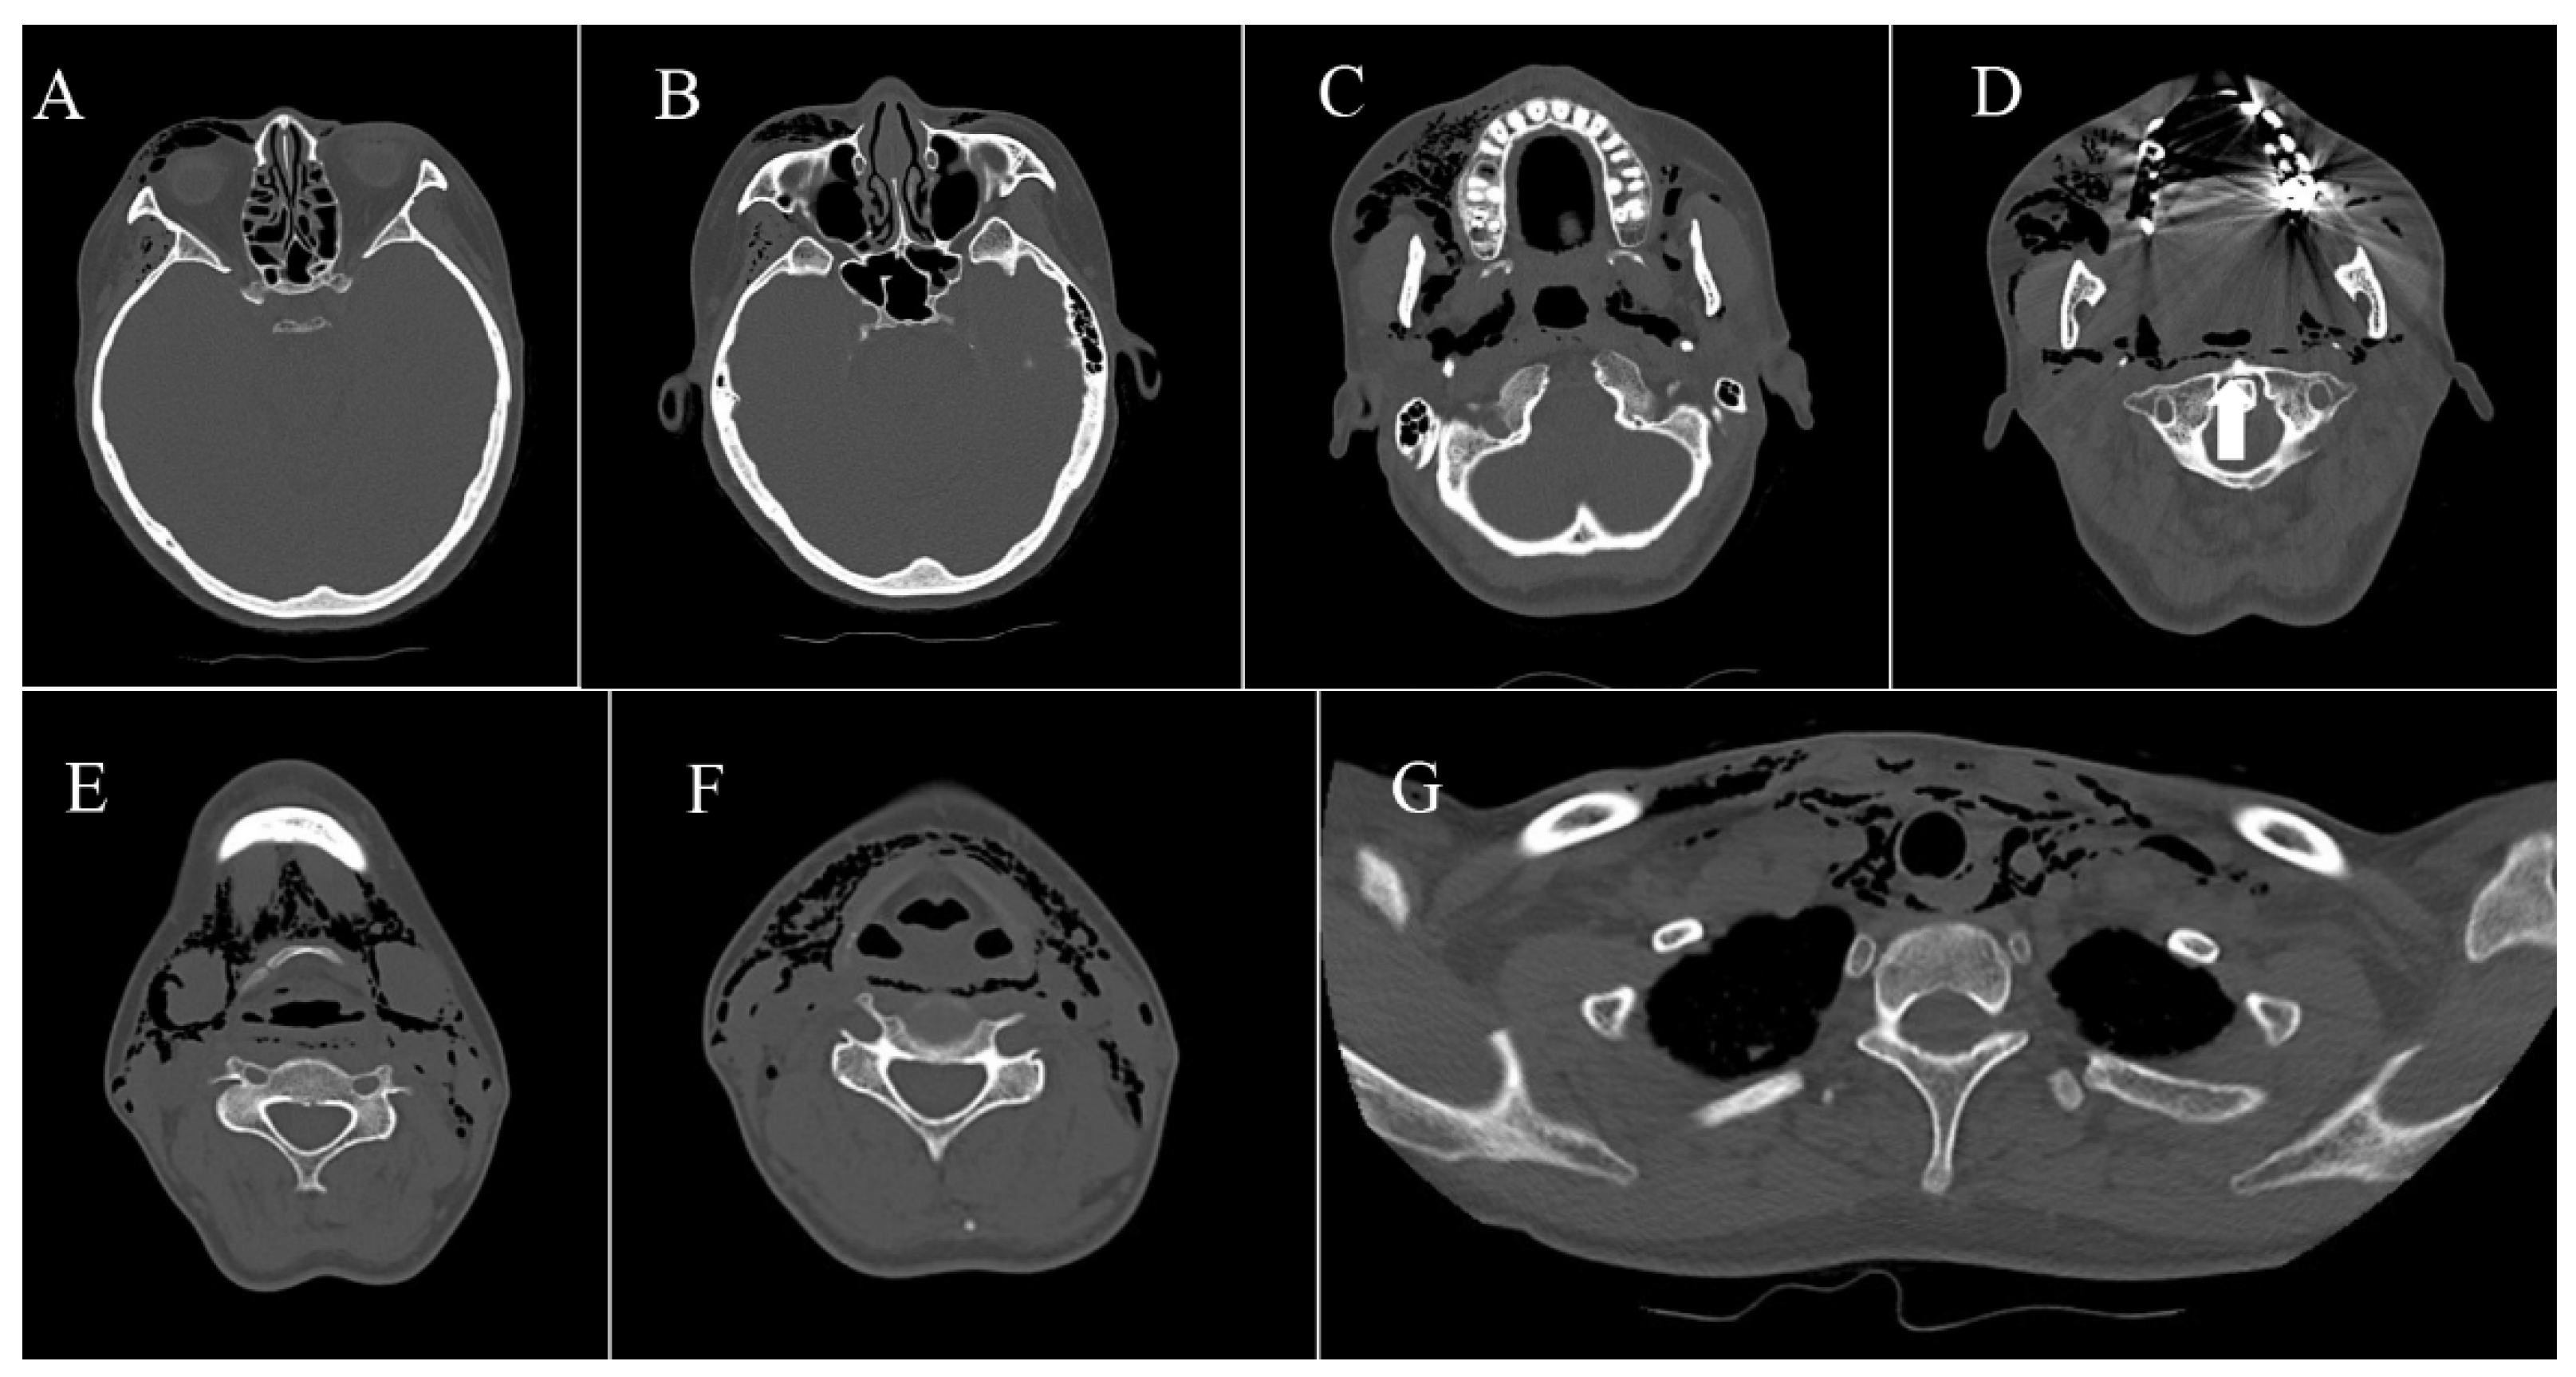

2.3.1. Case 1

2.3.2. Case 2

2.3.3. Case 3